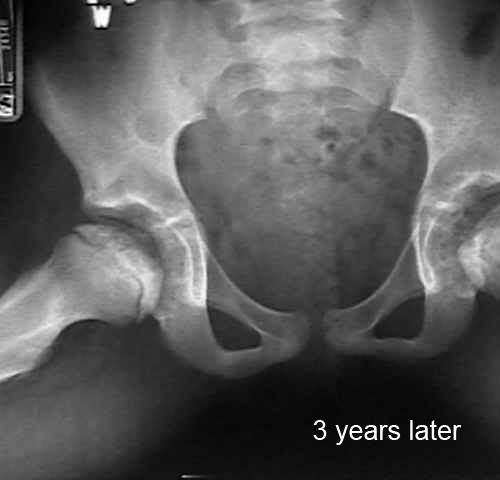

In contrast to what happens with adults, in children the dead bone is replaced by new bone thanks to a natural repair process. This entire process can last 1 - 5 years. The adjacent images show the development of the hip in a child with Calvé-Legg-Perthes disease.

hip Calvé-Legg-Perthes age 9